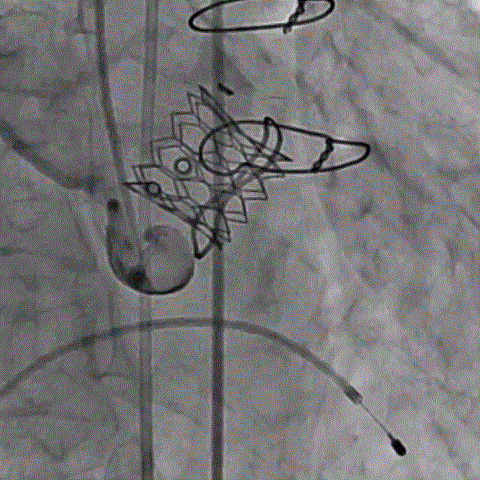

术前经详尽影像学重建和评估,该款人工生物瓣显影不理想,通过CT重建测量瓣环直径,评估冠脉梗阻风险。考虑到患者横位心,主动脉迂曲严重,最终选用经心尖入路,植入21# Renato球扩式瓣中瓣。手术顺利,瓣中瓣植入位置理想,功能表现出色,主动脉瓣峰值流速由术前3.4m/s下降至2.0m/s,平均跨瓣压差由术前32mmHg下降至8mmHg。经食道超声观察无瓣周漏及瓣中反流。

术前经详尽影像学重建和评估,CT重建测量瓣环直径,评估冠脉梗阻风险及外周血管条件。最终采用经股动脉入路植入21# Renato球扩式瓣中瓣。手术顺利,瓣中瓣植入位置理想,功能表现出色,主动脉瓣峰值流速由术前4m/s下降至2m/s,平均跨瓣压差由术前40mmHg下降至6mmHg。经食道超声观察无瓣周漏及瓣中反流。